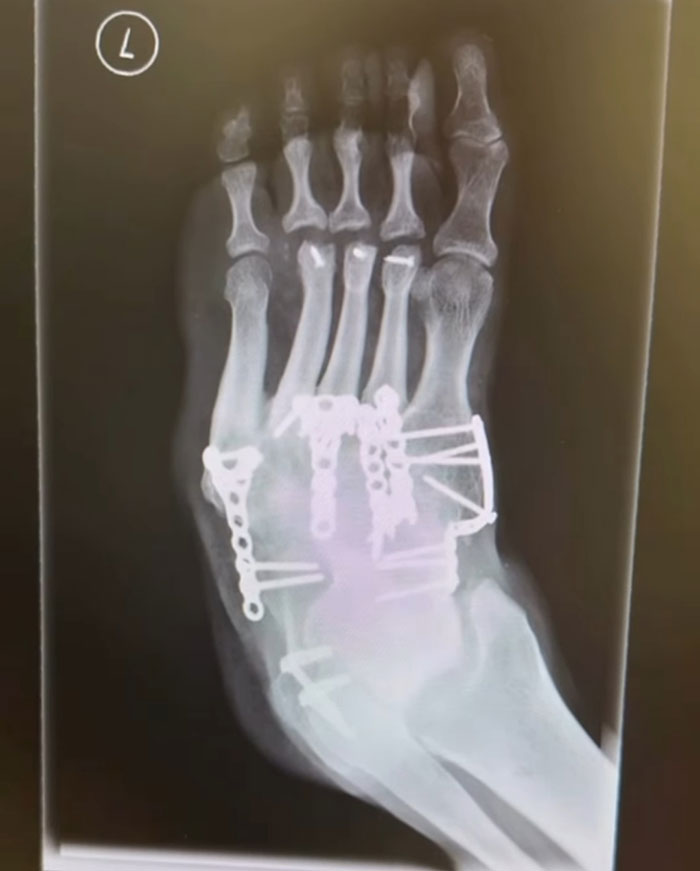

Hurrell underwent multiple surgeries in an attempt to fix the issues with his foot, but none were successful.

According to Tommy, each surgery only made his leg “deformed in every single way imaginable.”